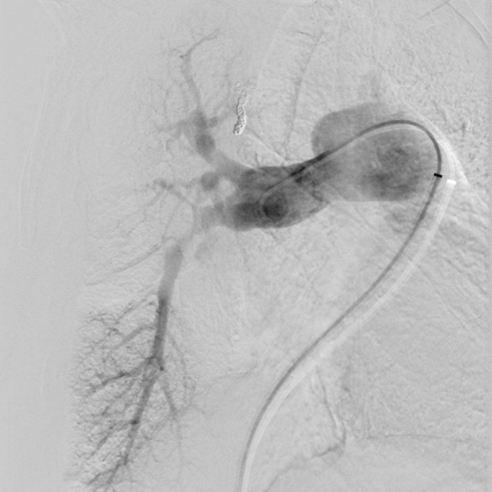

肺动脉造影:右肺上叶前段、后段肺动脉,中叶肺动脉、基底干肺动脉重度狭窄,尖段肺动脉迂曲扩张;左肺下叶肺动脉次全闭塞。

术前肺动脉造影